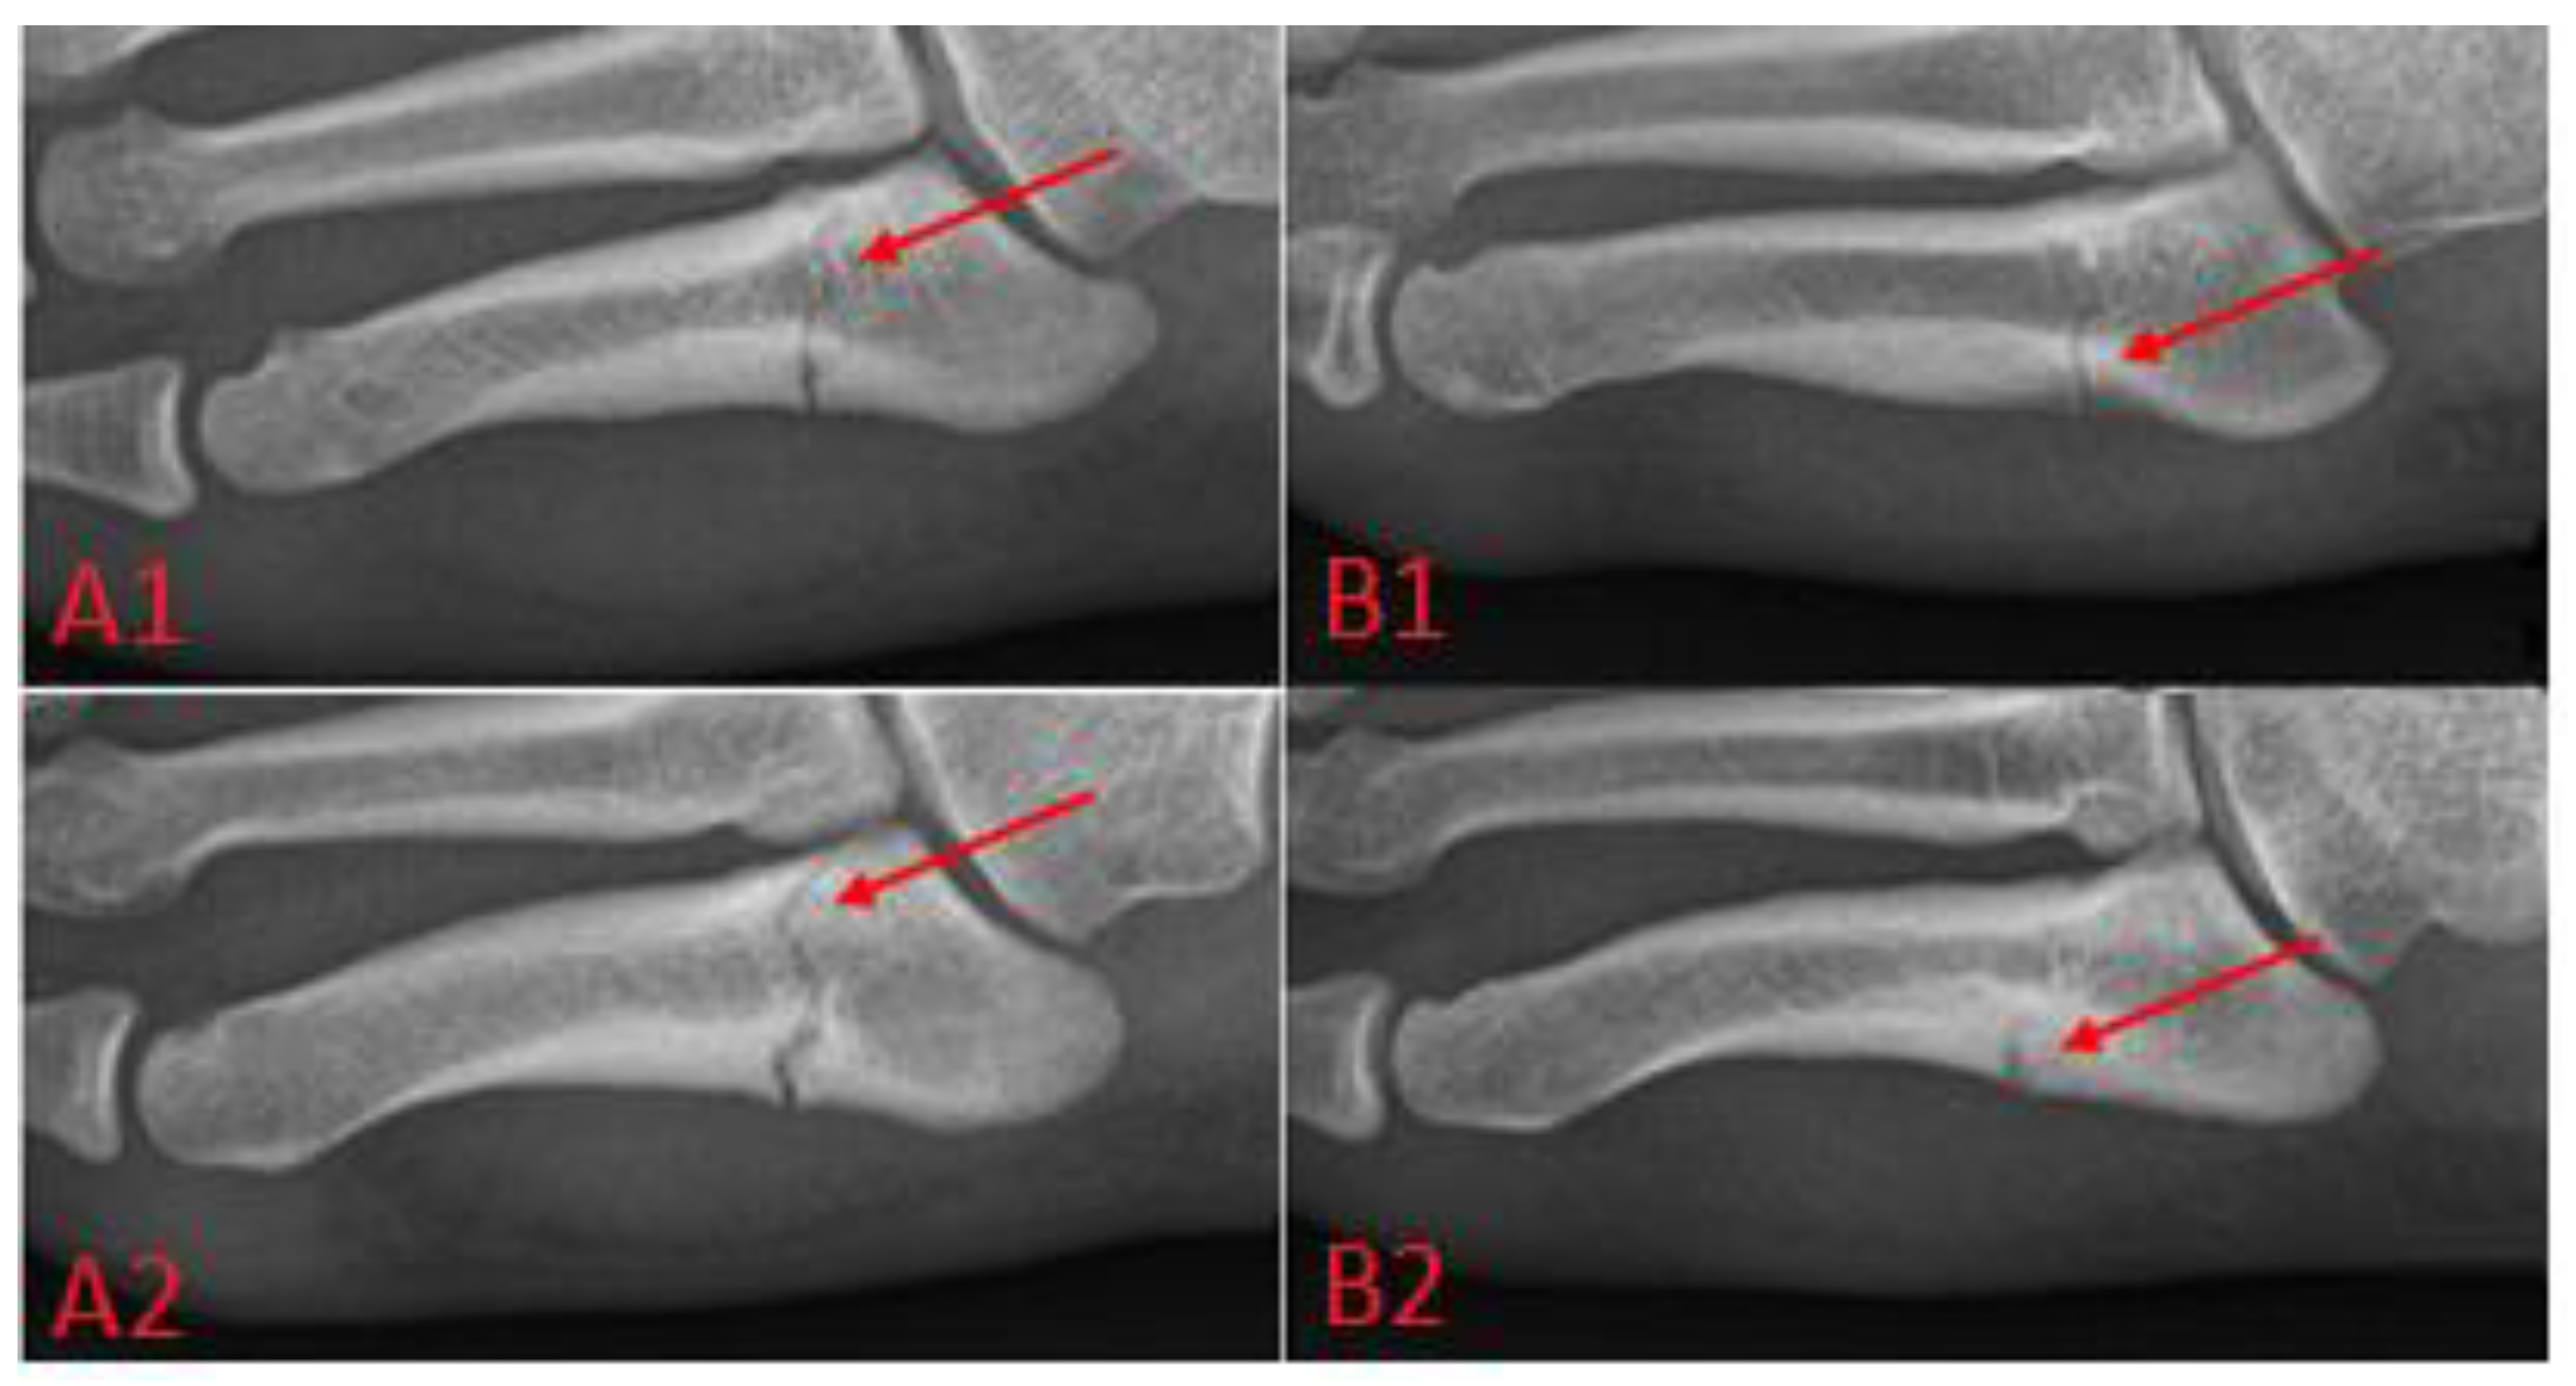

Metatarsal fractures, see Figure 3, can be treated surgically or conservatively; this paper focuses on the headless screw technique, in which the fracture is immobilized by the screw thanks to the differential pitch of the threads at the threaded ends, which leads to pulling the bone fragments together and, subsequently, to healing.

Figure 3. New classification of the proximal 5th metatarsal fractures, according to K. T. Lee: (A1) acute complete fracture, (A2) chronic complete fracture, (B1) incomplete fracture below 1 mm, (B2) incomplete fracture of 1 mm or more.